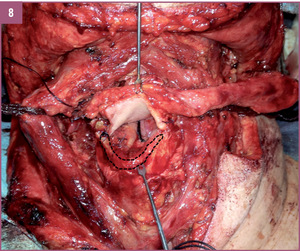

Zaplanowanie, wytworzenie, kształtowanie oraz implantacja zmodyfikowanego mikronaczyniowego płata małżowiny usznej opartego na naczyniach skroniowych.

A.M.: Tak, wspólnie uznaliśmy, że opracowanie takiej metody byłoby bardzo skuteczne i pomocne dla cierpiących na średnio lub wysoko zaawansowaną chorobę nowotworową nagłośni lub też średnio zaawansowanego raka krtani obejmującego nagłośnię. Doszliśmy do wniosku, że skoro do tej pory stosowano wiele nieskutecznych metod, nadszedł czas na wykorzystanie trójwymiarowej struktury odpowiadającej nagłośni i pochodzącej z ludzkiego ciała. Założyliśmy więc, że możemy wykorzystać zmodyfikowany fragment małżowiny usznej na naczyniach skroniowych z elementami skóry okolicy przed-, za- i nadusznej. Chodziło nam o to, by te elementy skórne odtwarzały boczne ściany gardła i część górną krtani, która również jest resekowana w przypadku raka nagłośni. Fragment małżowiny usznej z chrząstką w środku mógłby zatem po modyfikacji stanowić element elastyczny odpowiadający kształtowi i wielkości nagłośni. Liczne zabiegi przeprowadzone na zwłokach utwierdziły nas w przekonaniu, że wykonanie takich rekonstrukcji jest możliwe. Po kwalifikacji i przygotowaniu chorych na raka nagłośni w stopniu zaawansowania T2 i T3 z naciekiem na nasadę języka (nie większym niż 1-2 cm, gdzie kończy się możliwość rozsądnej rekonstrukcji), postanowiliśmy wykorzystać tę właśnie technikę.

CHARAKTERYSTYKA PRZYPADKU